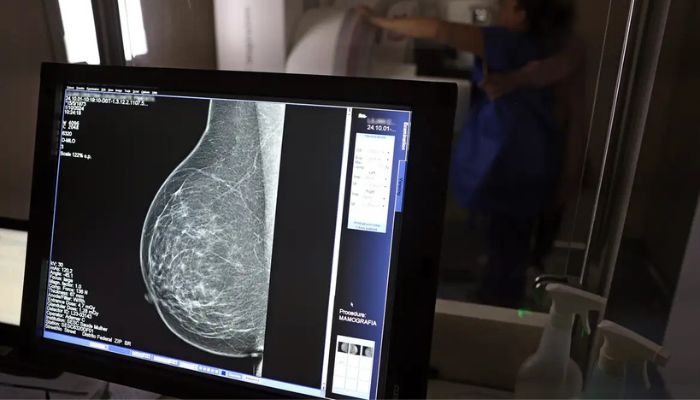

Falta de acesso a mamógrafos limita prevenção do câncer de mama

No mês de conscientização sobre o câncer de mama, um relatório destaca a importância de acesso igualitário ao rastreamento e tratamento da doença. Segundo o Atlas da Radiologia no Brasil, do Colégio Brasileiro de Radiologia e Diagnóstico por Imagem (CBR), o acesso aos mamógrafos ainda é um desafio.

O país tem 6.826 equipamentos registrados, sendo 96% em funcionamento. Metade deles está disponível no Sistema Único de Saúde (SUS), responsável por atender 75% da população. Isso equivale a 2,13 mamógrafos por 100 mil habitantes dependentes do SUS.

Na saúde suplementar, que cobre 25% da população, o cenário é mais favorável: 6,54 aparelhos por 100 mil beneficiárias, quase o triplo da rede pública. O Acre exemplifica essa disparidade — são 35,38 mamógrafos por 100 mil habitantes na rede privada, contra 0,84 no SUS.

O Brasil tem uma cobertura muito baixa de mamografias: 24%. O ideal recomendado pela Organização Mundial da Saúde é de 70%. Mesmo em lugares como o estado de São Paulo, que tem a maior concentração de mamógrafos do país, a taxa gira em torno de 26%.

Em setembro, o Ministério da Saúde ampliou as diretrizes de rastreamento, recomendando que mulheres entre 40 e 49 anos realizem mamografias, mesmo sem sintomas. De acordo com o Instituto Nacional do Câncer (Imca), mais de 73 mil mulheres recebem o diagnóstico de câncer de mama anualmente no Brasil.